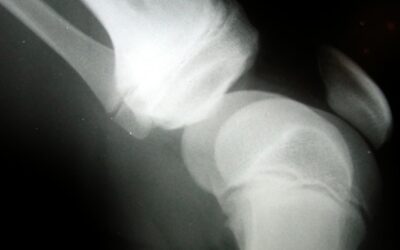

Osteoporosi, con denosumab sicurezza ed efficacia durature per almeno 8 anni

Nuove conferme sull’efficacia e sulla sicurezza a lungo termine di denosumab contro l’osteoporosi postmenopausale. A fornirle sono gli ultimi dati dell’estensione in aperto dello studio FREEDOM (Fracture Reduction Evaluation of Denosumab in Osteoporosis Every 6...